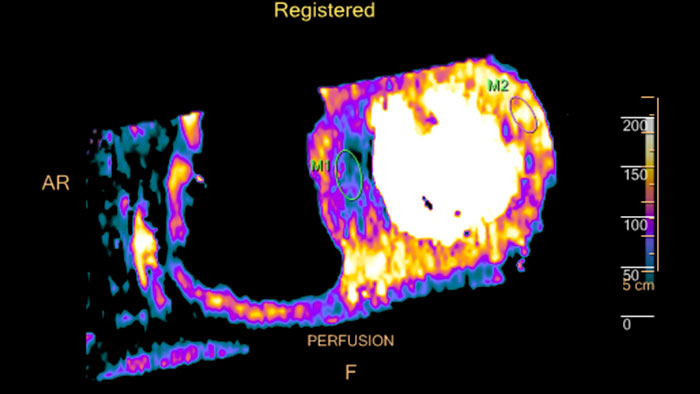

Fusing cardiac CT-MI images

Cardiac CT-MI Fusion incorporates support for myocardial perfusion imaging (MPI).

un-gated stress MI datasets simultaneously with the CT.

Dynamic color maps provide an assessment of myocardial risk